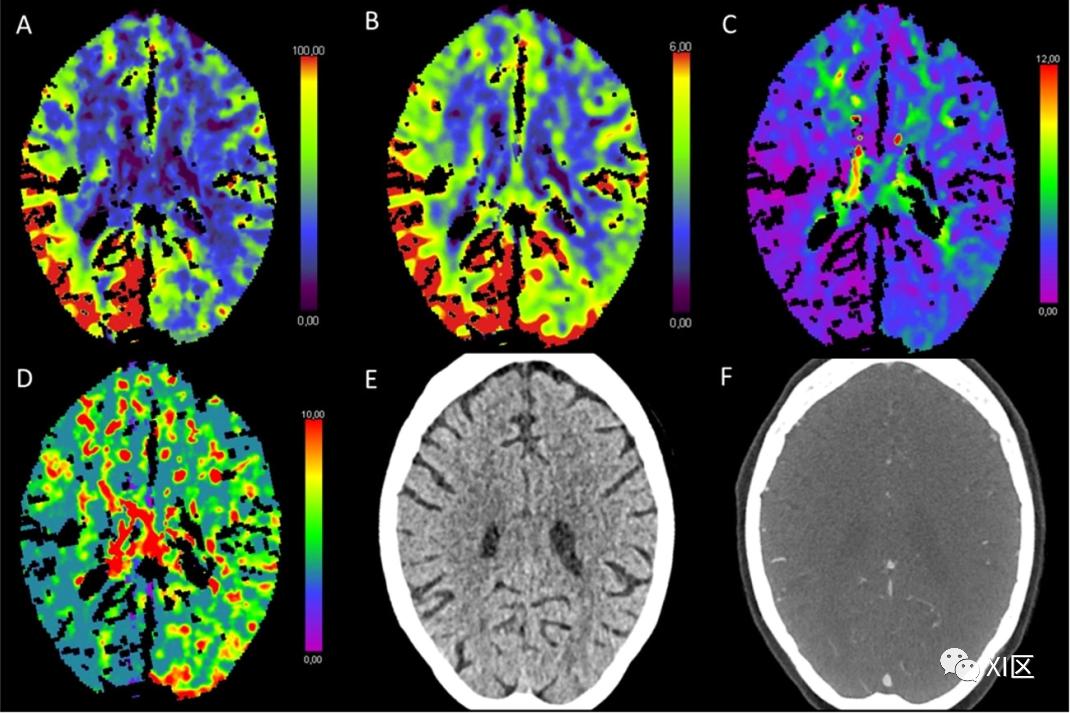

图1、图2、图3和图4给出了急性幕上卒中的例子。图5是一个恶性右侧MCA梗死的随访检查。

图1 脑部CTP产生的彩色编码图:(A)脑血流量量(CBF)[mL/100 g/min],(B)脑血容量(CBV)[mL/100 g],(C)Tmax [s],以及(D)平均通过时间(MTT)[s]。(E)CT平扫(NECT)和(F)动脉CT血管成像(CTA)。该患者接受了心导管检查,以关闭房间隔缺损。之后,该患者出现了左侧偏瘫。NECT显示灰白质分化略有减少。在右侧的大脑中动脉(MCA)区域,CBF和CBV降低,Tmax和MTT延长。CTA显示右侧颈内动脉远端闭塞。